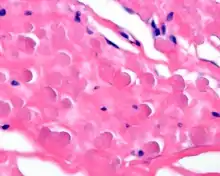

By microscopie view, there is an admixture of heavy dense bands of collagenous tissue dissected by fat and abnormal elastic fibers. The elastic fibers are often quite large and are easily identified. The elastic fibers are coarse, thick, and darkly eosinophilic, often fragmented into globules, creating a "string of pearls" or "pipe cleaner" appearance. Because of degeneration, the elastic fibers will appear as globules with a serrated or "prickled" edge.[3]

The elastic fibers will be highlighted by a Weigert or von Gieson elastic stains.[7]